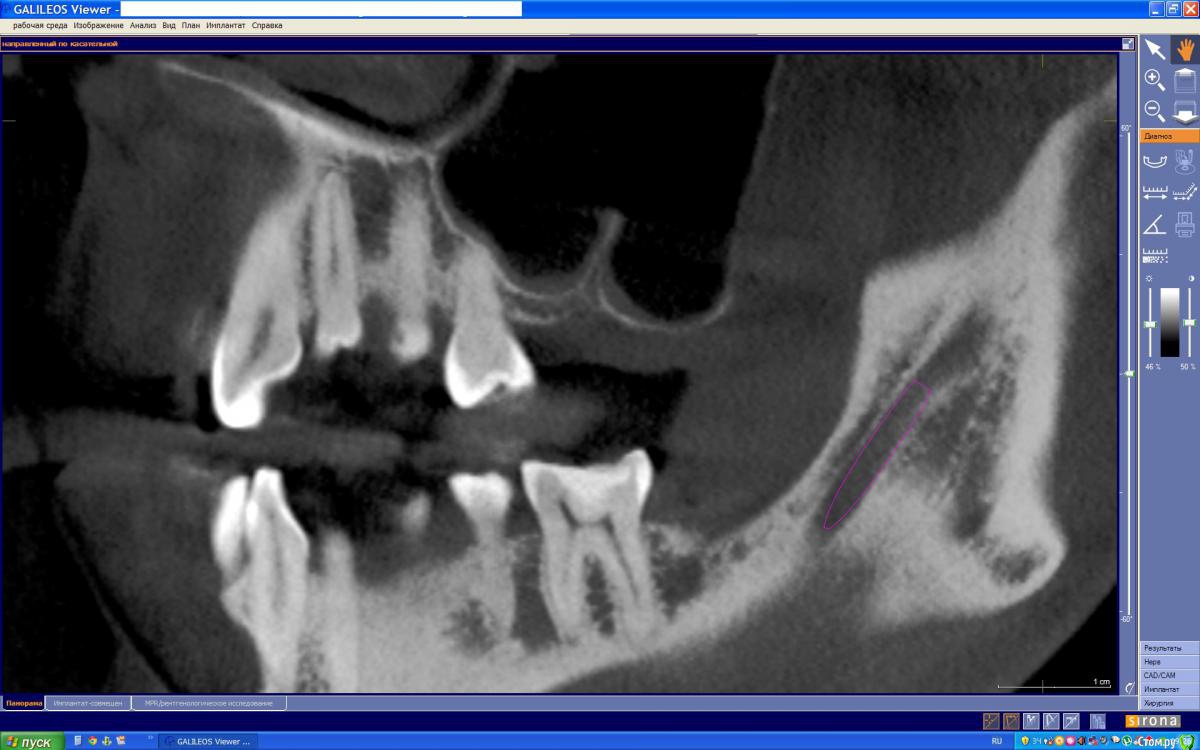

Azara Опубликовано 7 июня, 2015 Поделиться Опубликовано 7 июня, 2015 Здравствуйте, уважаемые специалисты. На консультации хирург-имплантолог изучив снимки КТ сказал, что случай сложный и из-за строения практически отсутствующей кости верхней челюсти нужно заполнять 2 полости, для чего потребуется сделать 2 окна в кости через которые будут проводится 2 операции по заполнению, и возможно что через год потребуется повторное заполнение. Ввиду физиологического строения, нехватку данного зуба я довольно остро ощущаю. Но к сожалению я морально не готова перенести такое добровольное "издевательство" над своим организмом. Врач сказал что на раздумья у меня полгода. Есть ли какая то другая возможность по восстановлению данного зуба без имплантации? Если все же только имплантация то другой способ синус-лифтинга? Зуб удален год назад. Заранее спасибо за ваше мнение. Ссылка на папку со снимками КТ https://yadi.sk/d/OksbhWPth8JVw И скриншоты с КТ Ссылка на комментарий